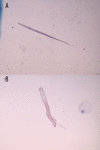

Case report: A young woman with history of asthma presented with complaints of nausea, vomiting, abdominal pain, wheezing, and dry cough. Physical examination revealed diffuse expiratory wheezing and mild diffuse abdominal pain without rebound or guarding. Laboratory results showed leukocytosis with eosinophilia. Stool studies showed Strongyloides stercoralis. Imaging revealed ground-glass opacities in the right upper and lower lobe along with an infiltrate in the lingular lobe on the left side. Bronchoscopy showed Strongyloides stercoralis. The patient was diagnosed with hyperinfection syndrome due to Strongyloides stercoralis most probably exacerbated by prednisone given for her asthma. Steroids were then discontinued and the patient was started on ivermectin. The patient improved with treatment. Repeat stool examination was negative for Strongyloides stercoralis.